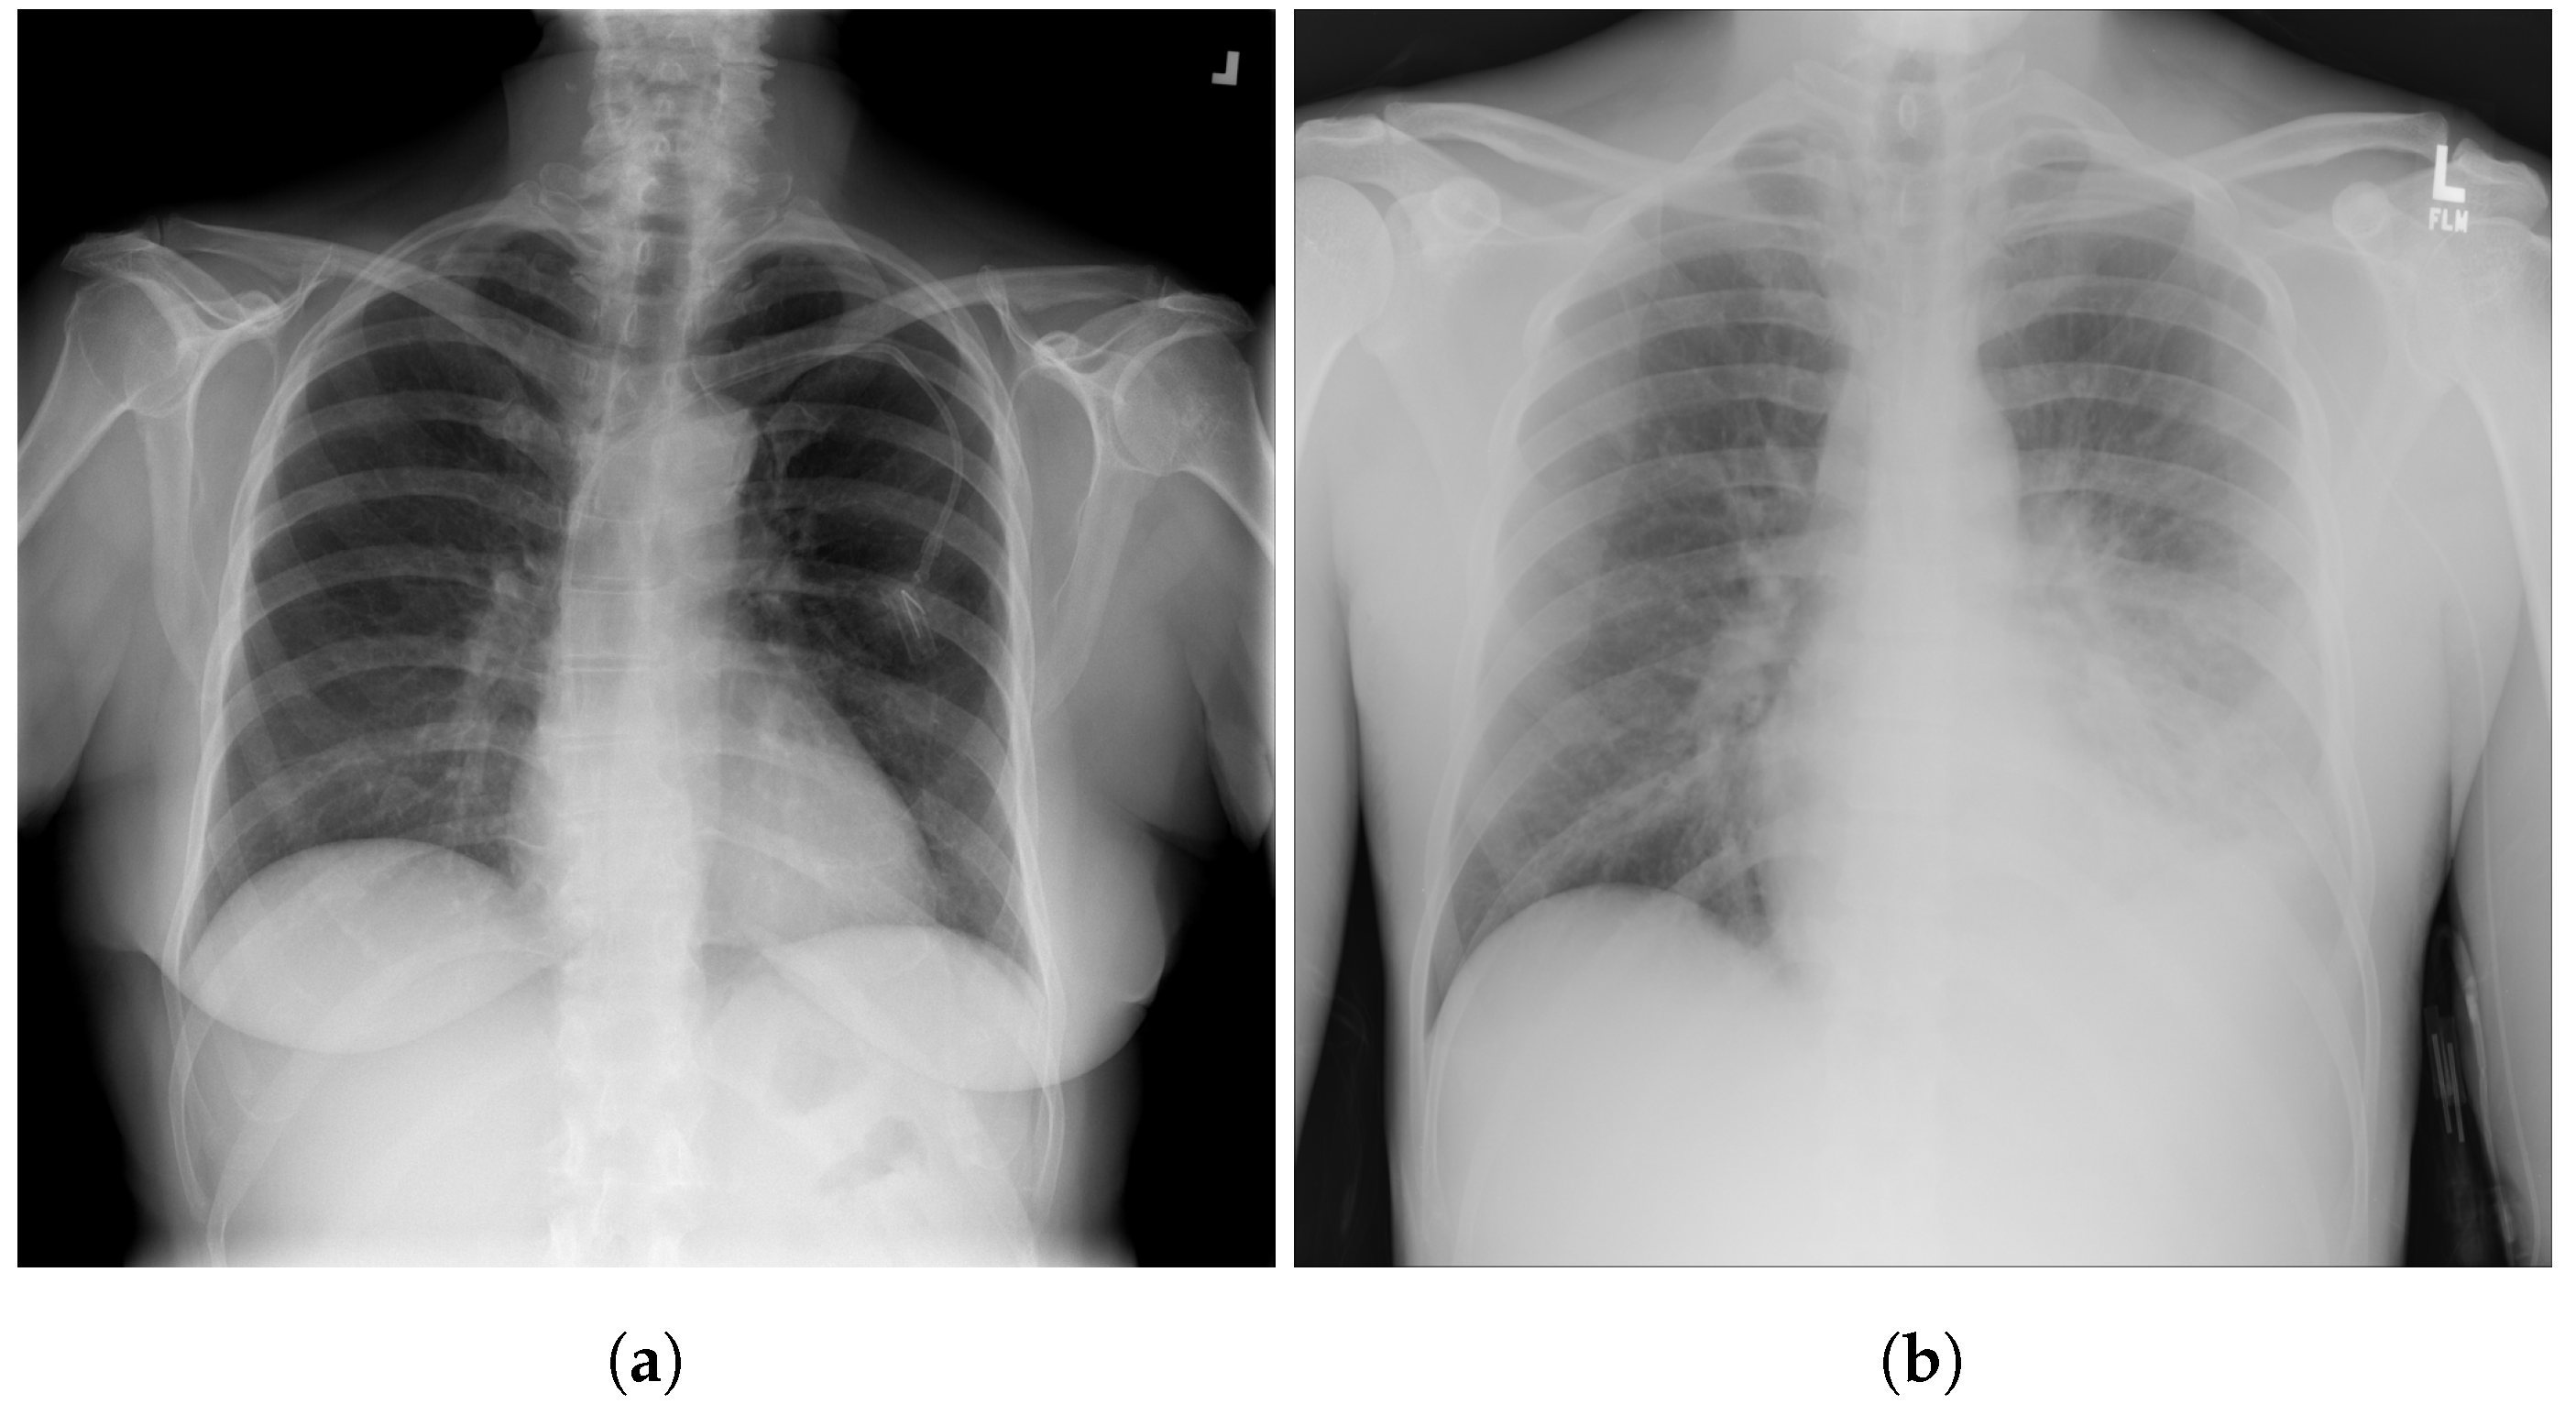

3.8. National Institute of Health (NIH)

3.9. Montfort Dataset